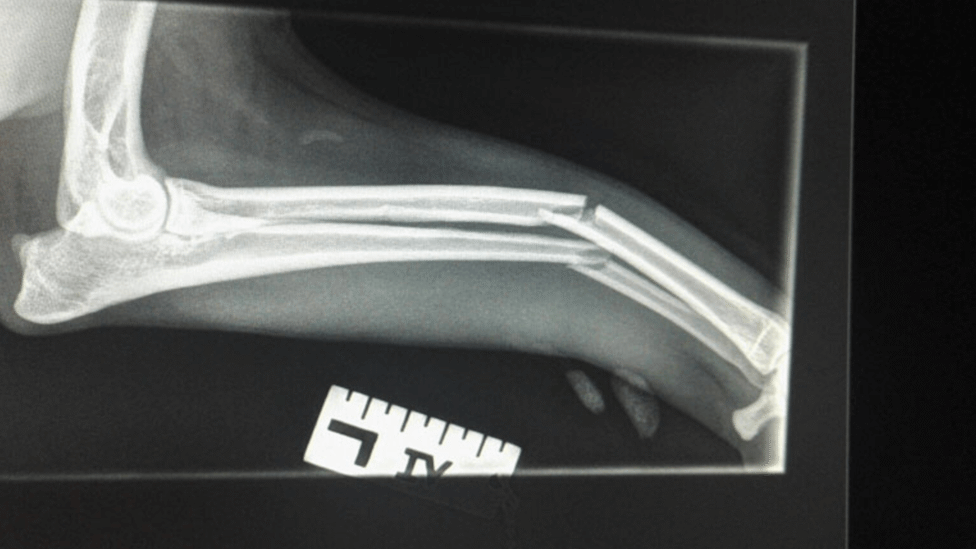

Y Fracture Repair

In a Springer Spaniel.